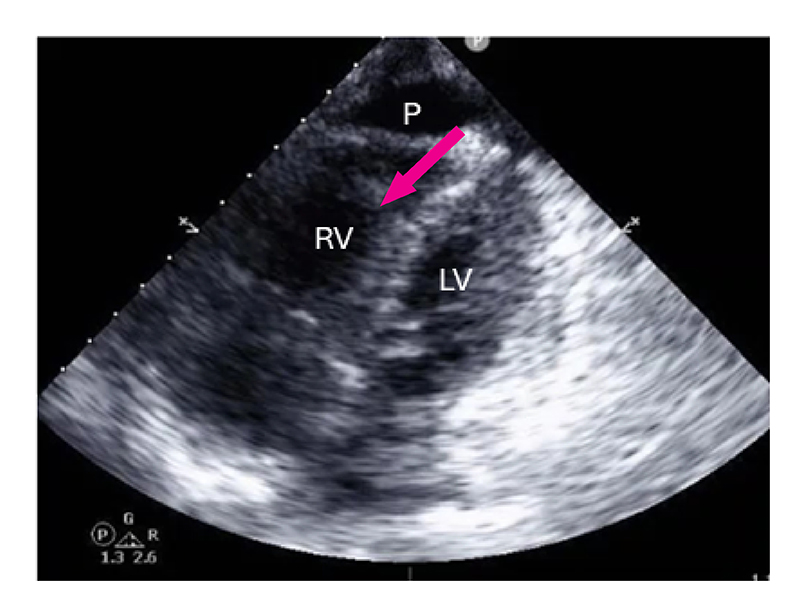

On presentation her temperature was 36.8°C, blood pressure was 102/74 mmHg, heart rate was 108 beats per minute, and oxygen saturation was 99%. She was noted on examination to have puffy hands, digital ulcers with dry gangrene, periungual erythema with normal nailfold capillaroscopy, ankle synovitis, and retiform purpura over the chest and both arms. Laboratory results showed elevated brain natriuretic peptide (7508 pg/mL), lactate (3.7 mmol/L), and sensitivity troponin T (21 ng/dL), plus mild proteinuria (urine protein-creatinine ratio, 0.35 g/g). An echocardiogram (Figure 2) demonstrated severe RV dilatation with severely reduced systolic function, severe tricuspid regurgitation, and small pericardial effusion; left ventricular ejection fraction was normal. The estimated pulmonary arterial systolic pressure was 55 to 60 mmHg, consistent with moderate pulmonary arterial hypertension (PAH). Computed tomography of the chest demonstrated interlobar septal thickening and multifocal lymphadenopathy.

Figure 2: 4-chamber view echocardiography, with findings consistent with moderate pulmonary arterial hypertension.

LV: left ventricle, RV: right ventricle, P: pericardial effusion.